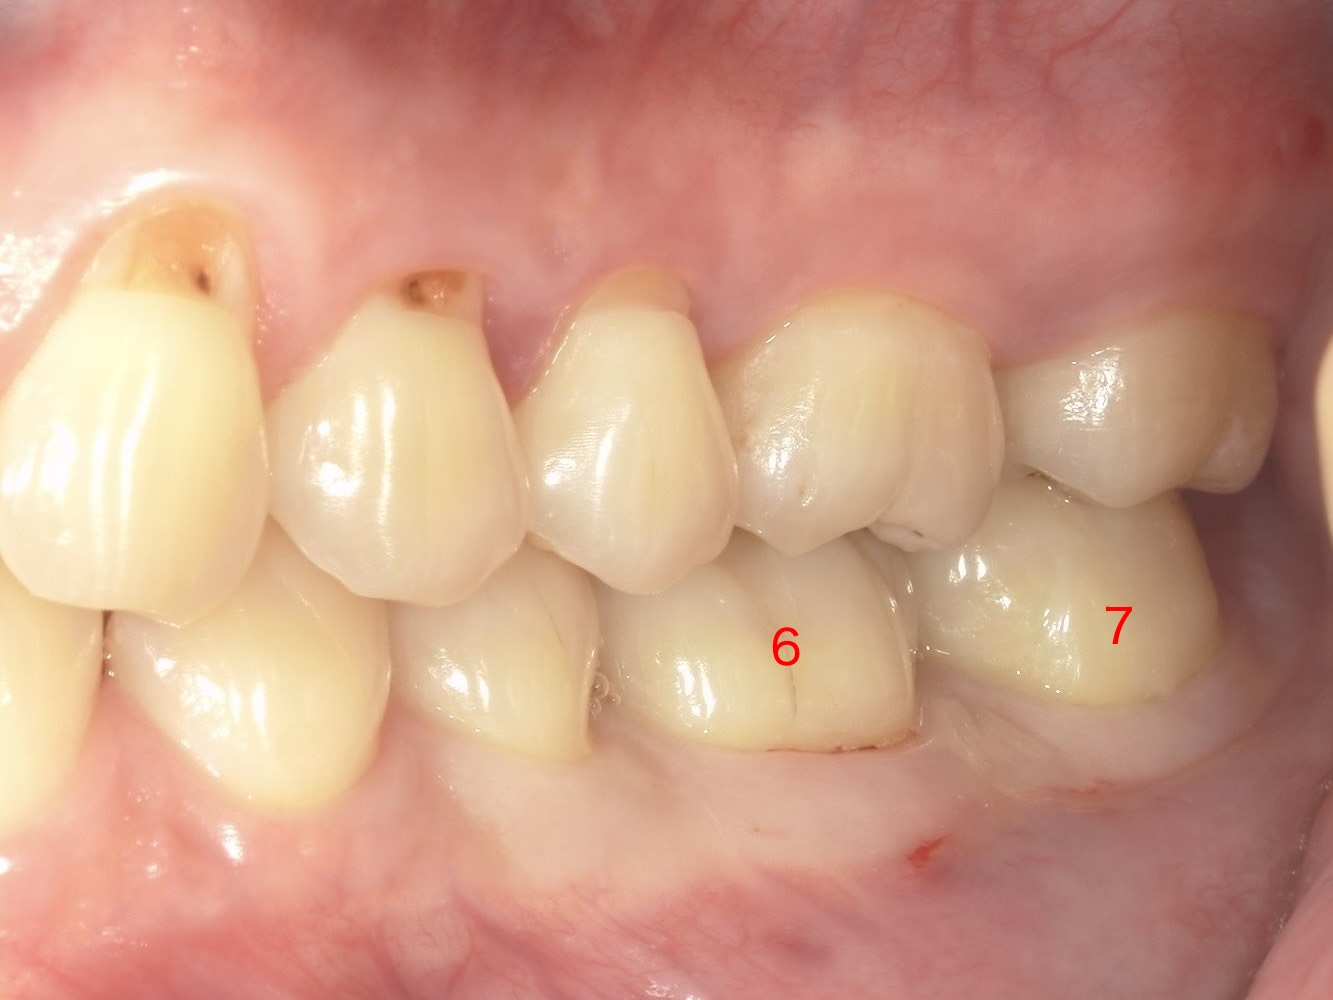

• 部位: 左下の奥歯(6番・7番)

• 症状: 6番頬側(ほっぺた側)中央に6mm、7番頬側(ほっぺた側)中央に7mm非常に深い歯周ポケットを確認。

レントゲン所見: 歯を支える骨が部分的に深く溶けてしまう「垂直性骨欠損」を確認。

※垂直性骨欠損:骨が水平に減るのではなく、部分的に深く掘れるように減っている状態

通常、健康な歯茎の溝は1〜3mm程度です。7mmとなると、歯ブラシはもちろん、通常の歯科医院でのクリーニング器具も届きにくく、放っておくと確実に歯を失う方向へ進んでしまいます。